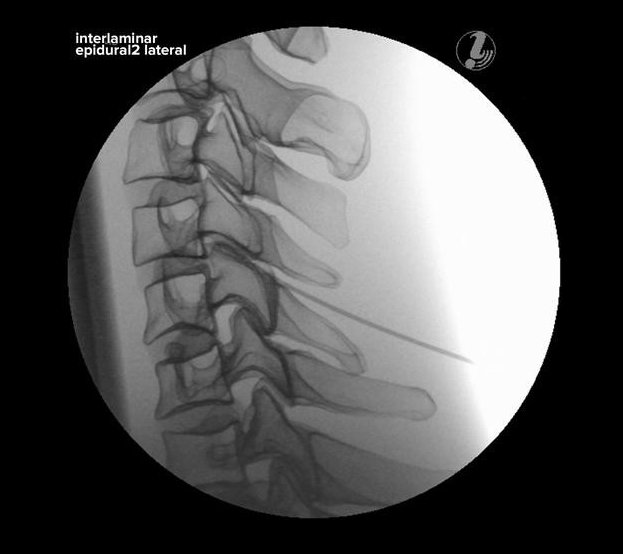

TRENAŻER ZNIECZULANIA ZEWNĄTRZOPONOWEGO W ODCINKU SZYJNYM POD KONTROLĄ USG

Trenażer znieczulania zewnątrzoponowego w odcinku szyjnym pod kontrolą USG umożliwia naukę diagnozowania źródła bólu, identyfikacji tkanki docelowej i narażonych struktur, przy użyciu USG i anatomicznych punktów. Prezentowany model to alternatywa dla pracy ze zwłokami. Model jest wytrzymały i zawsze dostępny do przeprowadzania ćwiczeń.

Trenażer prezentuje następujące kości:

• kości potyliczne

• Kręgi C1 – Th2

• Żebro 1 i 2

• realistyczne obrazy X-ray

• realistyczna symulacja znieczulenia

CECHY: Trenażer znieczulania zewnątrzoponowego w odcinku szyjnym pod kontrolą USG